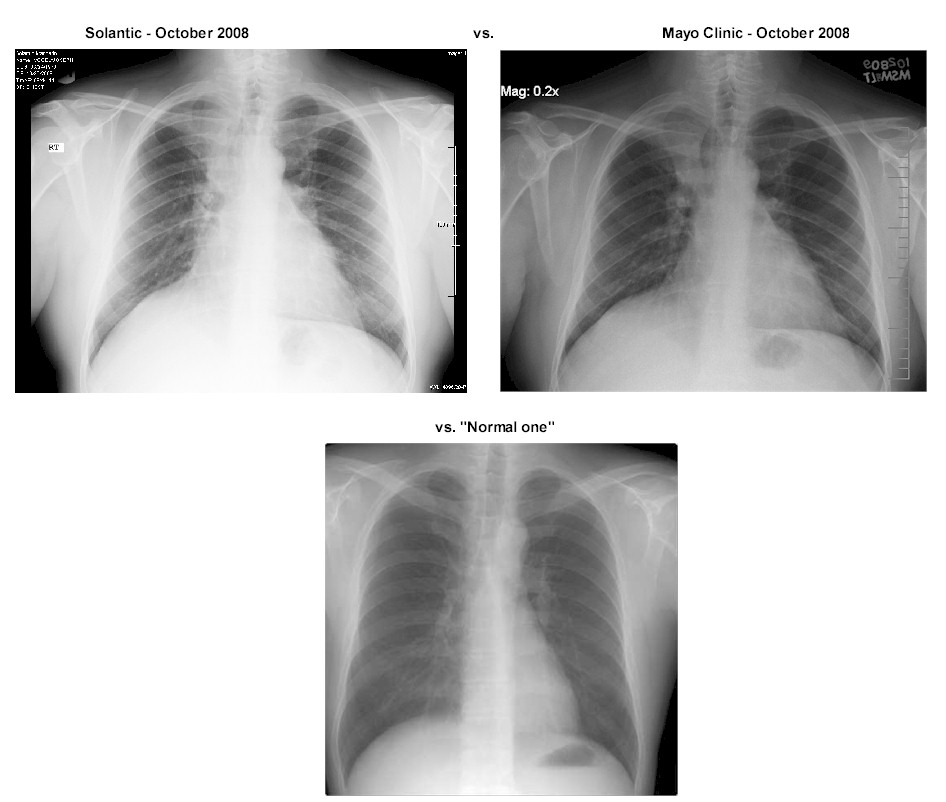

X-Ray of my chest done by Solantic and indicated as

"normal lung" in October 2008:

When you compare this to the example of a real normal one above, you can see how

the right side it shifted up and the upper right area is not as dark.

The dark area indicates "air" in the lung (when you get a chest x-ray they ask

you to breath in deep). Also note on the left hand side you see more of a

full lung, remembering that the heart is in front of the lung on that side so it

does not show up as dark.

But you can tell something is not quite right with the right lung presentation.

Nonetheless, the Solantic doctor indicated it as "normal

lung".

X-Ray of my chest done by Mayo and indicated as

"abnormal lung" in October 2009:

So, as you can see, basically the EXACT same!

Which in one way was good since it had not gotten worse, BUT it was the exact

same so Solantic totally missed it!

Arg!

So, let's compare ....